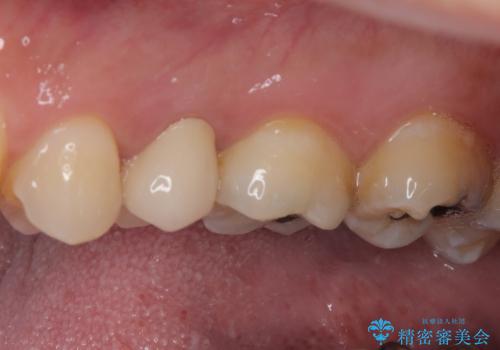

- 放置していたむし歯を治療したいとのことで来院された患者様です。

仕事が忙しいことを言い訳に虫歯を放置してきたものの、強い痛みを感じたことがあったため、重い腰を上げて来院されたとのことでした。

強い痛みのあった歯は、既に神経組織が失活しており根管治療が必要でした。

反対側の歯は、歯根だけが歯肉に埋もれて残っている状態のため、抜歯が必要な状態でした。